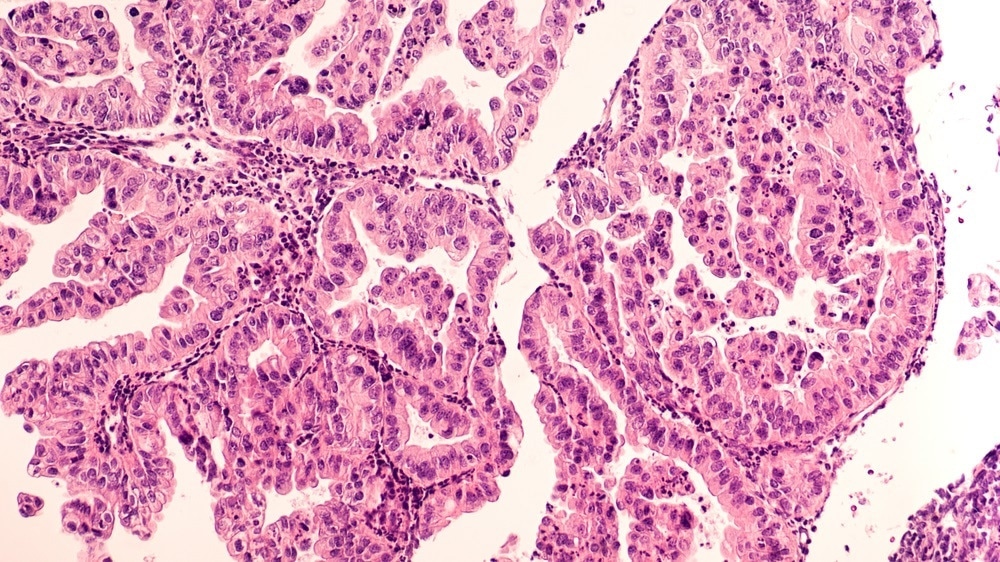

That's done through the analysis of frozen sections. These are pieces of tissue that are sent to a laboratory and then they're frozen,  sectioned, and stained. The pathologist then looks at the stained tissue section under a microscope to determine if all the cancer has been removed or not during that surgical procedure.

The problem is that this procedure can take a long time. Sometimes the surgeries are extended by 35 to 40 minutes because you have to wait for the frozen section analysis to be done. It can also be quite subjective because this process of freezing the tissue quickly during surgery to be able to get a section for the pathologist to look at using a microscope can cause some changes to the tissue histology and the cytology. It can be hard for a pathologist to precisely evaluate if there's cancer or not in that region of the tissue section.